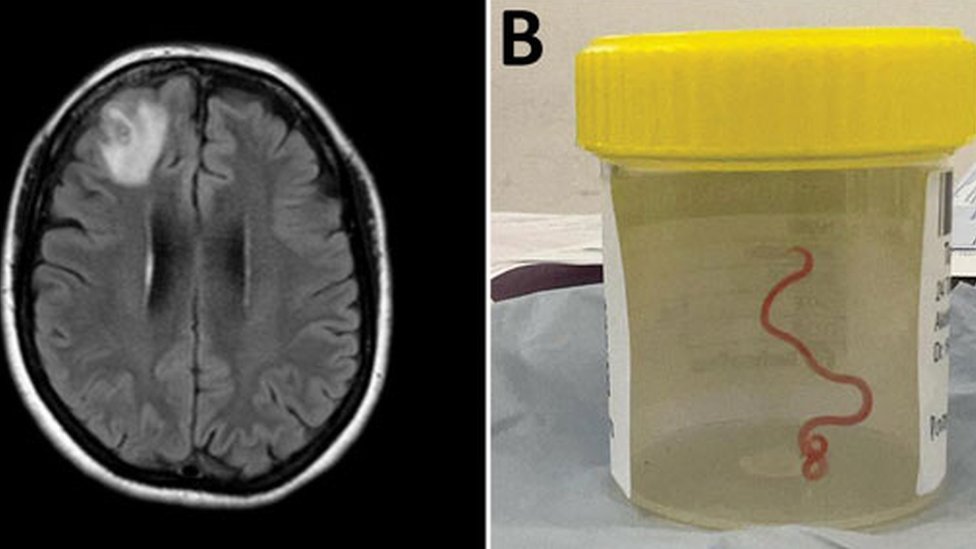

Iz mozga žene u Australiji, lekari su tokom operacije izvukli živog crva, dugog osam centimetara, što je prvi takav slučaj u svetu.

„Struktura poput strune“ izvučena je iz oštećenog tkiva prednjeg dela glave engleskog pacijenta tokom operacije u Kanberi, jednom od većih australijskih gradova prošle godine. Crveni parazit je, pretpostavlja se, moguće bio u mozgu ove žene do dva meseca.

„Svako ko je prisustvovao operaciji se šokirao kada je hirurg pincetom izvukao vijugav, strani organizam, dug osam centimetara, crvene boje.

Skeniranjem joj je otkriveno „atipično oštećenje u desnom prednjem delu mozga“.

Biopsijom u junu 2022. godine saznali su i uzrok njenog stanja.